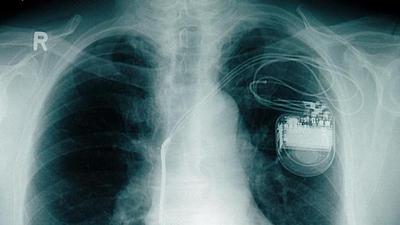

Mais de 30% dos idosos morrem por doença cardiovascular, diz SBC

Dados divulgados pela Sociedade Brasileira de Cardiologia – SBC – mostram que, nesta década, os idosos morrem mais de doenças cardiovasculares do que a média da população, que está em 30%, com 400 mil óbitos por ano.